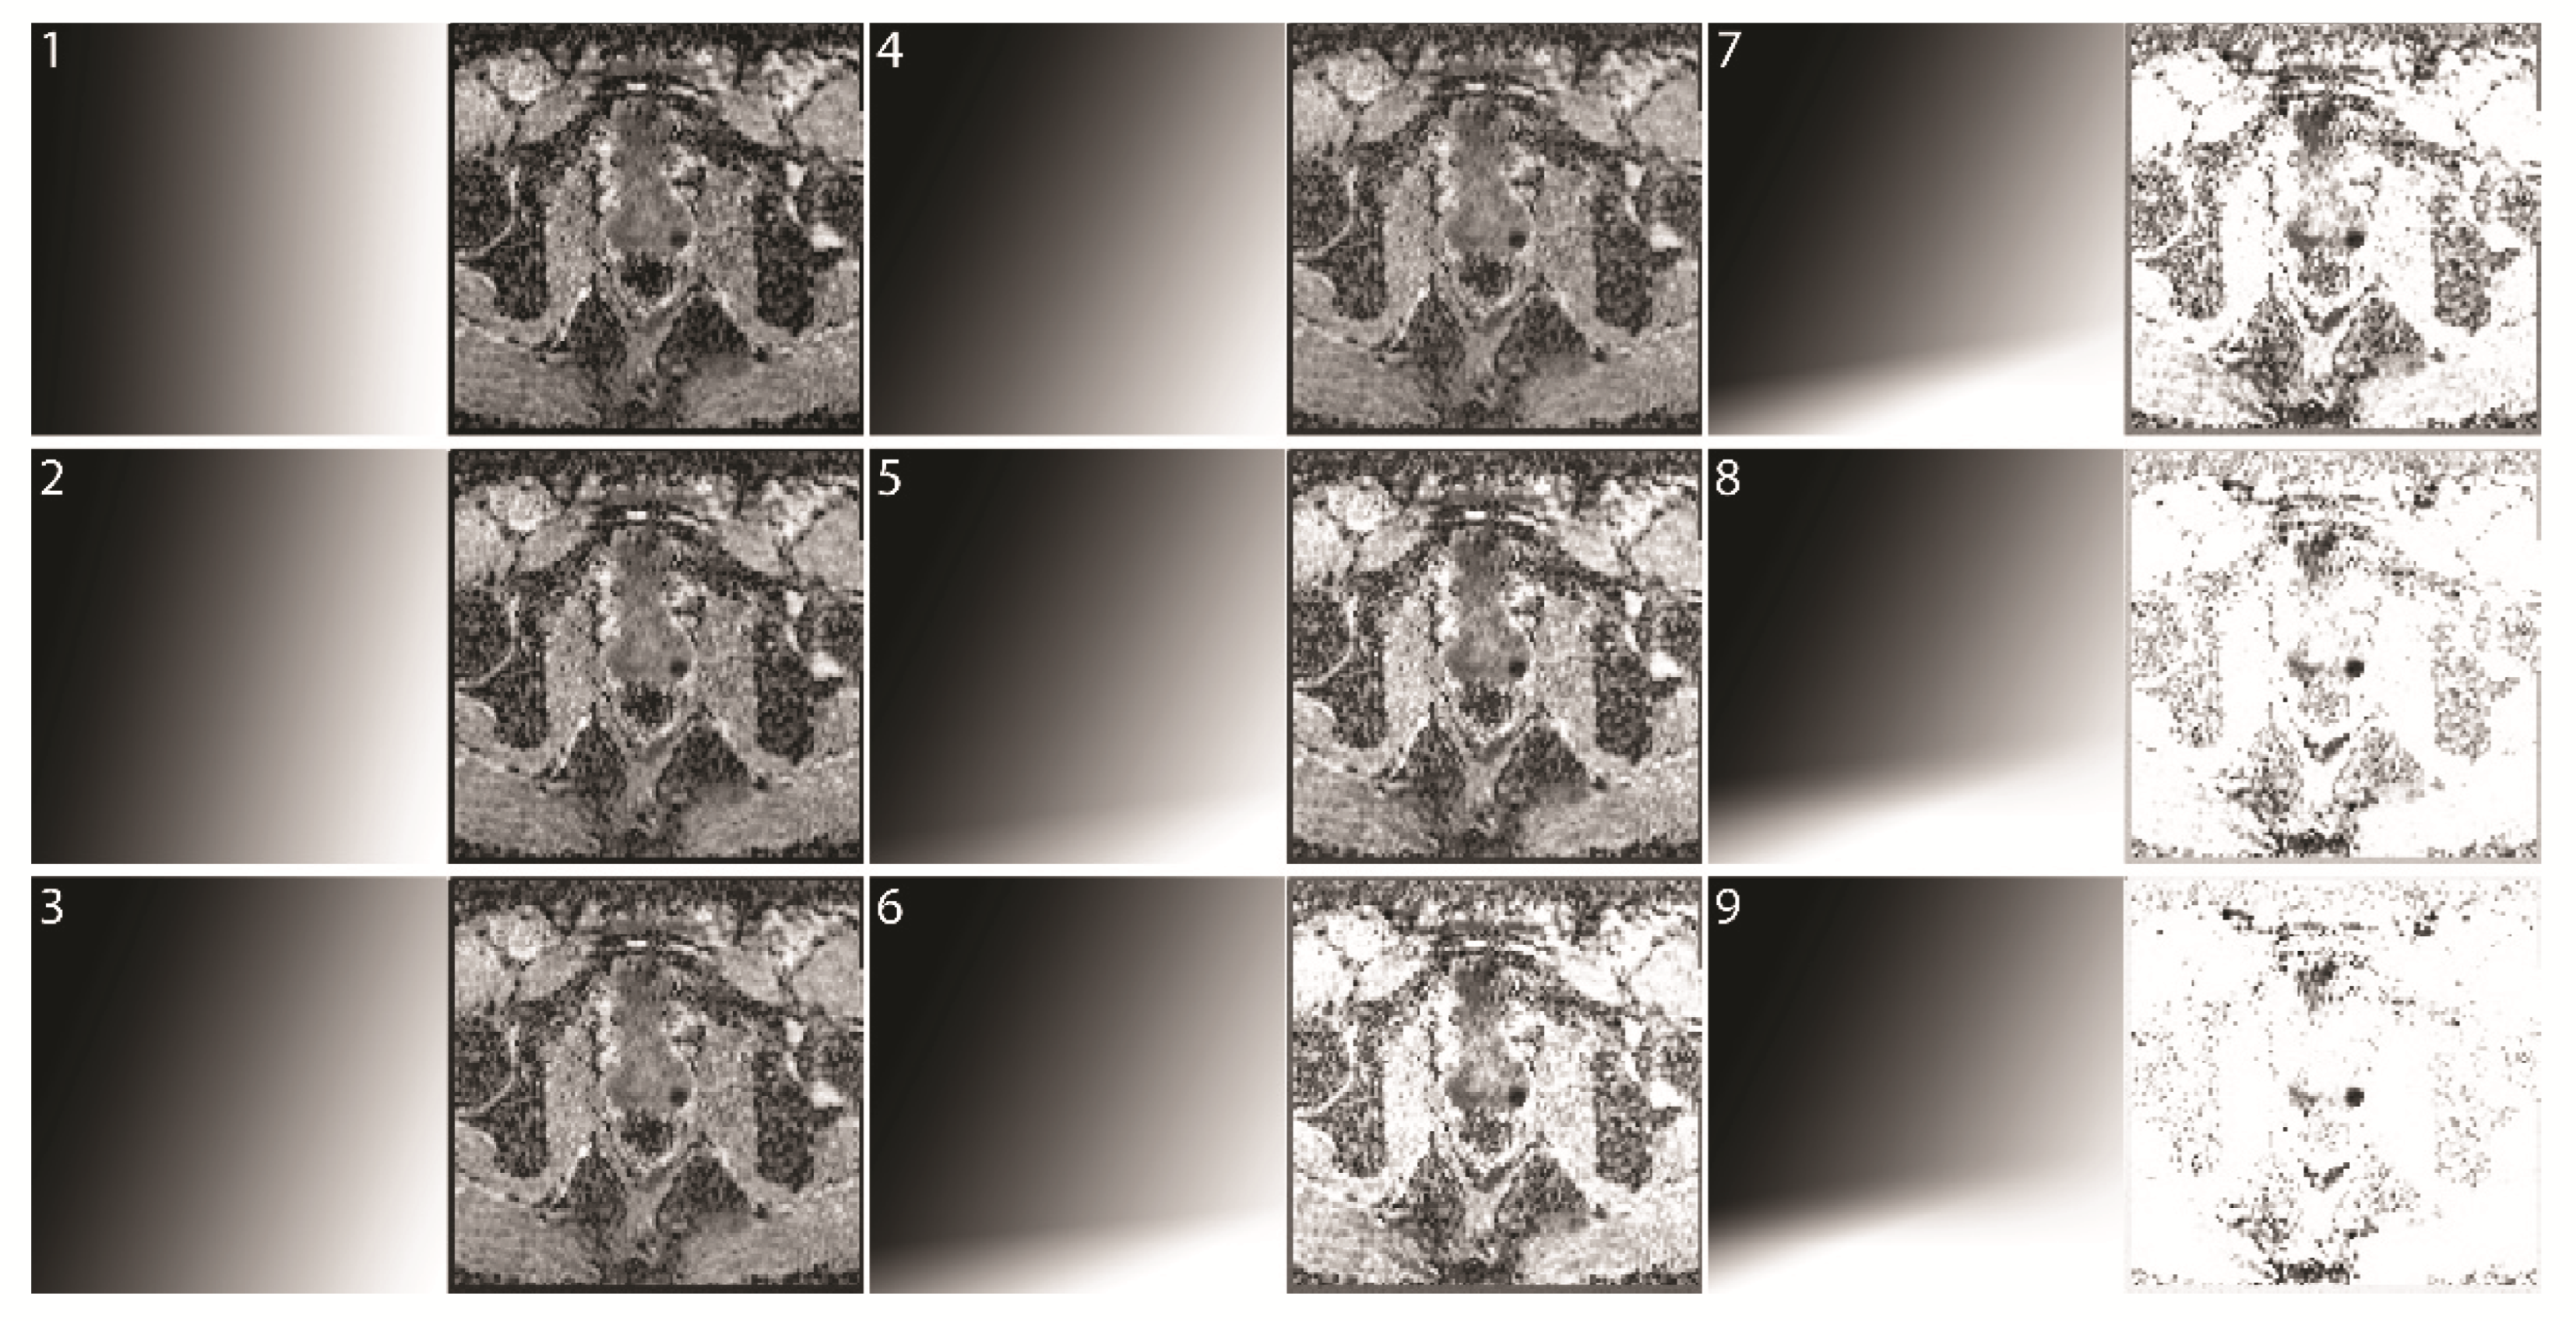

Figure 4. Increasing strengths of background suppression. Examples of different readouts from a mcDI dataset created from hbDWI and the corresponding ADC (map 19). The selected map is shown on the left and the resulting mcDI on the right. Map 1 has a strict vertical readout and therefore yields the original ADC image. In the following maps, the gradient is tilted clockwise in increments to include the DWI value. Additionally, another gradient is added at the bottom to suppress the background.

Group 1 serves as the baseline performance of the readers. Although only clearly negative (PI-RADS 1 or 2) and positive (PI-RADS 4 or 5) examinations with the corresponding biopsy results were included, we expected an accuracy of less than 100% due to the mono-planar approach, missing clinical information, and nonclinical setting of the study. The readers had to decide whether a significant PCa was present. To eliminate the risk of increased accuracy in one of the groups due to a training effect, the patients and three groups were distributed randomly, each read was at least one week apart, and the results of the previous reads were not known to the observers. The second evaluation was done in the same manner. All observers received ten training patients (that were not part of the test dataset), their PI-RADS score, and histology. The reading time for each patient was recorded. The readers could select from nine different maps and the corresponding mcDI via a sliding scale (Figure 4). Map 1 was the original ADC image. In each subsequent map, the influence of the DWI and background suppression was increased.

The readers were able to select from different maps (Figure 4). They preferred intermediate background suppression. Readers 1 and 3 preferred map 5 (number of reads with the corresponding map (m) for readers 1;3: m1 = 2;0, m2 = 5;11, m3 = 9;8, m4 = 13;16, m5 = 62;63, m6 = 19;8, m7 = 1;6, m8 = 0;0, and m9 = 1;0), while reader 2 preferred a more conservative approach, with m3–m5 being his preferred maps (m1 = 0, m2 = 1, m3 = 33, m4 = 38, m5 = 37, m6 = 2, m7 = 0, m8 = 0, and m9 = 0).

In our study, the readers could select from various maps with different weightings of the suspicious tissue and the background. The readers were found to favor an intermediate weighting of the images. One explanation for this lies in the loss of the background information necessary to correlate the tumor with its location in the prostate due to the strong suppression of the background in a mcDI setting.

In routine clinical practice, a combination of a low and a high b-value is seldom read in isolation. It is standard to calculate an ADC, and in many cases, a higher b-value is calculated to enhance the sensitivity for tumor detection [13,14]. These calculations are, however, purely mathematical and highly standardized; therefore, no knowledge of the underlying tissue is used to enhance the images, especially for a specific study. The present study produced two findings that are commonly known to radiologists but are not yet implemented in image creation. First, tumor conspicuity increases with the increasing signal in hbDWI and decreasing intensity in ADC. We used this characteristic by tilting the axis of the grayscale gradient to combine the information of both images (Figure 3). Second, most of the background has a low signal in the hbDWI, while there are no tumor voxels below a certain threshold. This no-tumor zone was used to reduce the background without losing contrast in the tumor (Figure 4).